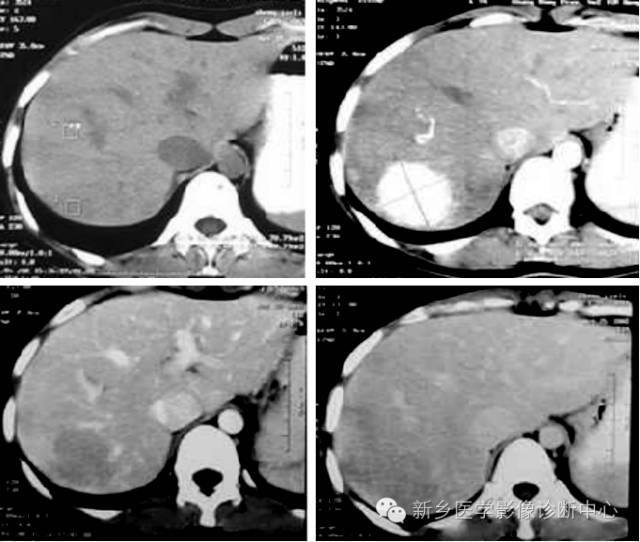

CT表现特点:病灶多为圆形或类圆形,边界清楚但无假包膜。平扫呈均匀低密度,增强扫描病灶边缘呈明显的不连续的结节状强化,强化区域进行性向中心扩展。延迟扫描病灶呈高密度充填。较大的病灶中心可见始终不充填。

血管瘤与其他富血供肿瘤的鉴别:①血管瘤的强化与血管相当。②血管瘤在延迟影像上呈持续强化。③血管瘤有周围结节样强化,其环内缘呈波浪状,而肝转移瘤其强化环内缘凹凸不平。④血管瘤增强后呈进行性持续性、向心性强化,无“周围洗脱”现象。